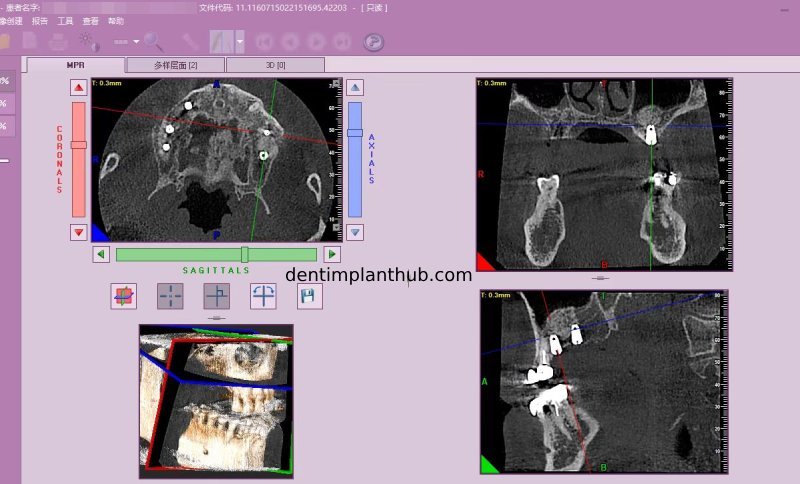

Screenshot of patient's CT on March 14, 2024